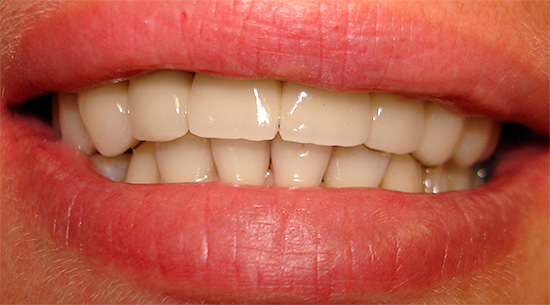

Deve-se ter em mente que o conceito de "implantação basal", como tal, hoje é coisa do passado. Existe um protocolo de carregamento imediato, que inclui várias tecnologias para restauração dentária, dependendo do quadro clínico. É adequado para restaurações simples e múltiplas, incluindo a ausência completa de dentes - um exemplo correspondente é mostrado nas fotografias abaixo:

O protocolo de carregamento imediato implica a realização da operação em uma única etapa, bem como o carregamento instantâneo (imediato) da prótese - daí o nome (implantação de dentes com carga imediata, implantação em estágio único, sinônimos simultâneos e outros).

Esse protocolo também é usado para restaurações únicas, mas é mais adequado para pacientes com desdentamento completo ou falta de segmentos de dentes inteiros. Além disso, nos casos em que são observados processos atróficos no tecido da mandíbula, a técnica também pode ser aplicada através do uso de partes fortes e estéreis do osso (falaremos mais sobre isso mais adiante).